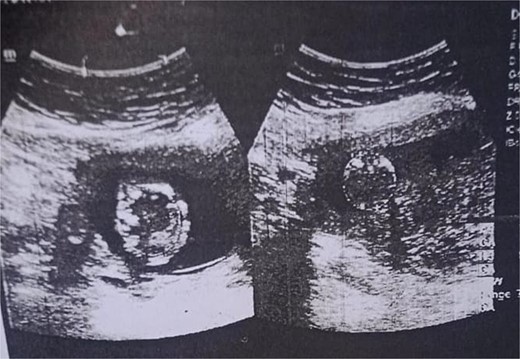

The functional impairment significantly impacts the quality of life of the patient, and the aggressive nature of the tumor requires surgical intervention. A multidisciplinary team was involved, including orthopeadic surgeons, oncologists, radiologists, and obstetricians. The surgical procedure involved a medial sub vastus approach for marginal resection of the tumor (Fig. 4), followed by a mega-prosthesis knee with 10 mm polyethylene (Fig. 5). Intraoperatively, the tumor was found to be confined to the medial femoral condyle without the involvement of surrounding soft tissues. Alignment was meticulously checked, the wound was closed in layers, a drain was placed, and a knee immobilizer was applied. Denosumab was not used considering the pregnancy.

Marginal resected tumor margin and frozen section were taken for confirmation of tumor margin.

The X-ray after surgery showed a mega prosthesis with good implant alignment.

Postoperative care included continuing antibiotics for two weeks, pain management, and initiating a passive range of motion exercises the next day. The immediate postoperative period was uneventful, and postoperative X-rays confirmed the proper placement and alignment of the prosthesis. The patient was mobilized with the help of physiotherapy, and her mobility gradually improved. She was scheduled for regular follow-up visits to monitor her recovery and the status of her pregnancy.